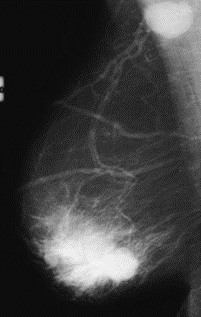

Na którym obrazie rentgenowskim sutka uwidoczniono zmianę patologiczną w obrębie węzłów chłonnych?

A. Obraz 2

B. Obraz 3

C. Obraz 4

D. Obraz 1